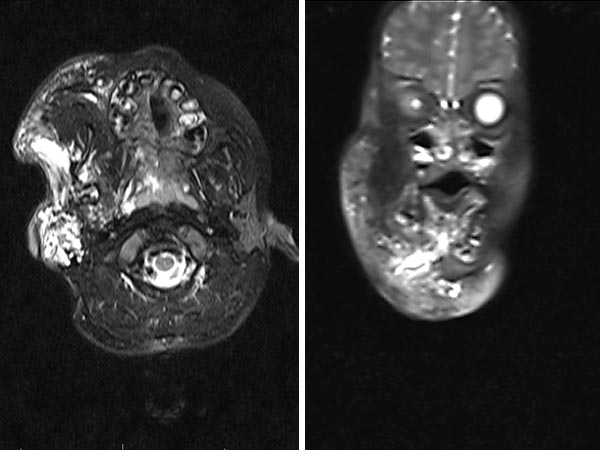

Die T2-gewichtete, fettgesättigte MRT im Alter von 2 Monaten zeigt das ganze Ausmaß der zystischen LM im axialen Bild (links) und im koronaren Bild (rechts).